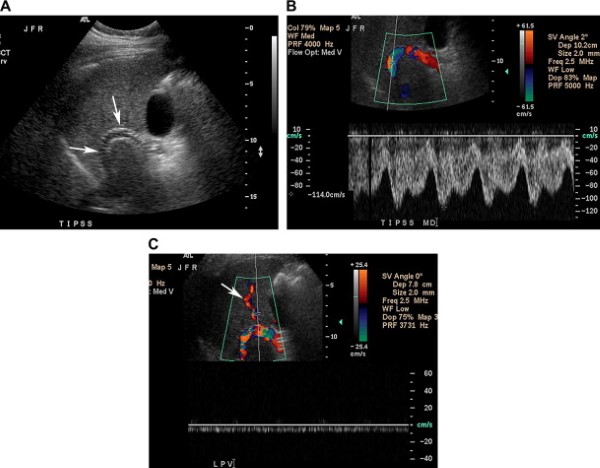

Tốc độ dòng chảy trong TIPS khi đo bằng Doppler phổ có thể biến đổi đáng kể với tốc độ trung bình trong các shunt thông là 95 cm/s ở đoạn cuối tĩnh mạch cửa và 120 cm/s ở đoạn giữa shunt [2]. Hướng dòng chảy trong thân tĩnh mạch cửa chảy về gan, tốc độ tĩnh mạch cửa tăng nhẹ trên 40 cm/s [2, 62]. Dòng chảy ở nhánh tĩnh mạch cửa phải và trái điển hình rời gan hướng tới TIPS, mặc dù việc này có thể biến đổi phụ thuộc vào mức độ xơ gan (Hình 23)[63].

Hình 23. TIPS thông bình thường ở bệnh nhân nam 42 tuổi có tiền sử xuất huyết dạ dày ruột vì giãn tĩnh mạch xơ gan do viêm gan C và nghiện rượu. (A) Ảnh thang xám cho thấy TIPS với 2 thành tăng âm của stent, không có dấu hiệu huyết khối trong lòng (mũi tên). (B) Ảnh siêu âm Doppler màu cho thấy dòng chảy có nhịp đập trong TIPS thông bình thường, tốc độ đỉnh 114 cm/s. Tốc độ này trong khoảng kỳ vọng bình thường 90 tới 120 cm/s. (C) Ảnh Doppler nhánh tĩnh mạch cửa trái cho thấy dòng chảy rời gan và hướng tới stent. Dấu hiệu này khẳng định TIPS có chức năng bình thường.